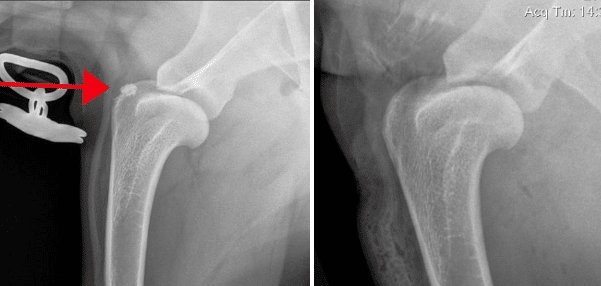

The X-ray (radiograph) below (to the left) shows a dog supraspinatus with mineralization within it and the post-operative image (to the right).

Most cases of supraspinatus tendinopathy do not have mineralization like the case above, and hence are not diagnosed with X-rays (radiographs). Most cases require use of ultrasound, MRI, or diagnostic arthroscopy for diagnostic confirmation. The arthroscopy images below show an enlarged supraspinatus tendon in a canine impinging upon the biceps tendon. The canine supraspinatus is pushing the biceps from right to left.